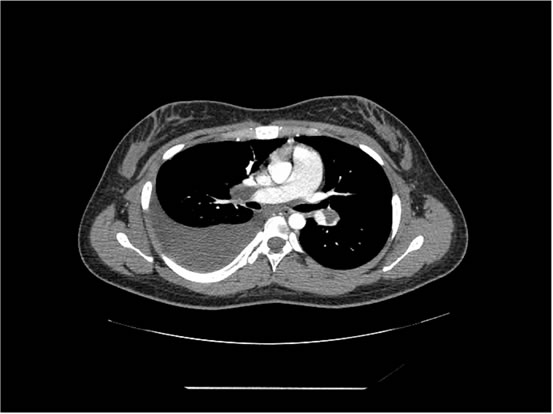

We ordered a CT scan with infusion of the chest

I will show you 12 CT-scan cuts.